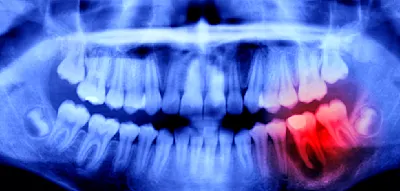

Als Zahnschmelz bezeichnet man die harte, sichtbare Schicht, welche die Zähne umgibt. Diese Schutzschicht ist täglich gefordert, da zahlreiche Nahrungsmittel Fruchtsäure enthalten, die den Zahnschmelz besonders angreifen. Sie weicht die äußere Schicht der Zähne auf und verursacht Löcher.

Es entsteht Karies, welche auf Dauer die Zahnstruktur zerstört. Der Körper kann diesen Verlust nicht ausgleichen: Ist der Schmelz einmal abgetragen, ist er bisher unwiederbringlich zerstört. Aktuell gängige Behandlungen wie Fluoridlacke lindern lediglich die Symptome des Zahnschmelzverlustes. Das Gel aus Nottingham könnte Zähne in Zukunft nachhaltig reparieren und schützen.